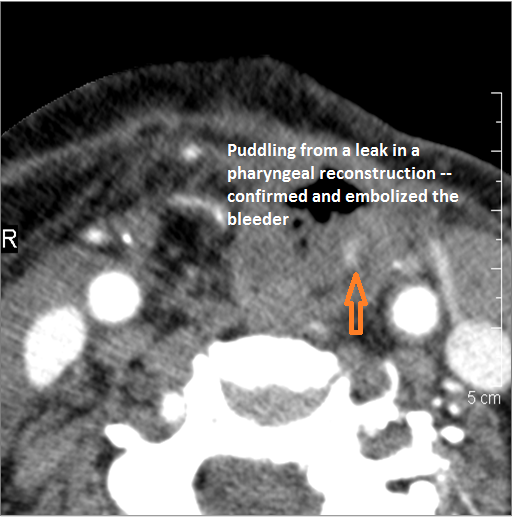

There is evidence of active extravasation or a contained leakage from an arterial source. [Yes/No]